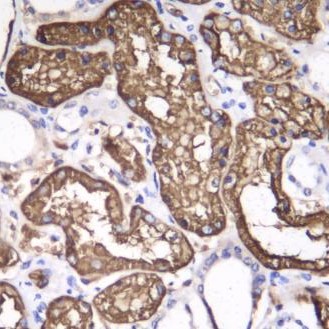

Formalin-fixed, paraffin-embedded human kidney tissue stained for Src (Phospho-Y529) using 60291 at 1/100 dilution in immunohistochemical analysis.